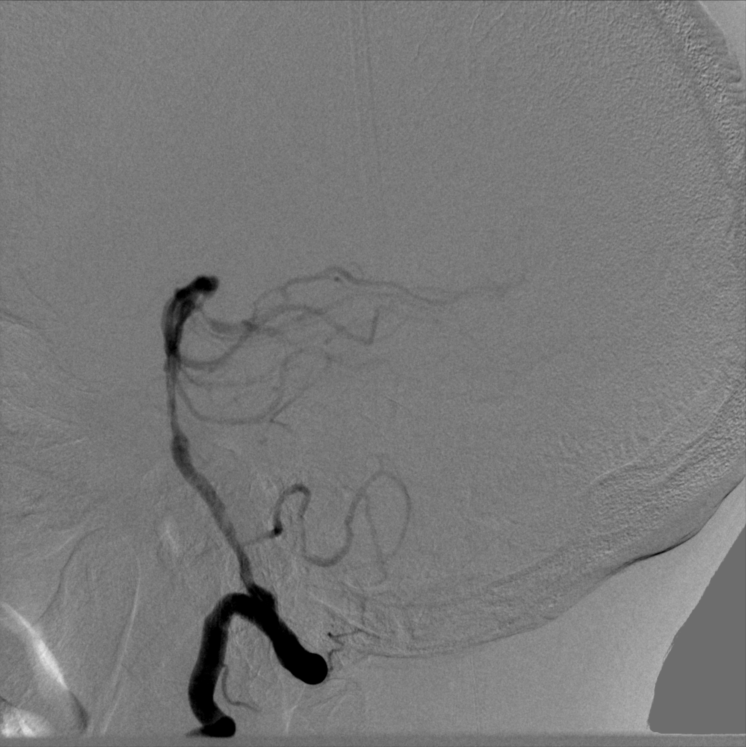

2022-10-11我院头颈DSA:

➤ 左侧颈内动脉造影:左侧颈内动脉C1段局限性狭窄约90%,C4-6段斑块形成,左侧大脑中动脉下干M2段狭窄约50%。

➤ 右侧颈内动脉造影:右侧颈内动脉C4段局限性膨大,溃疡斑块形成,C5段狭窄约50%。